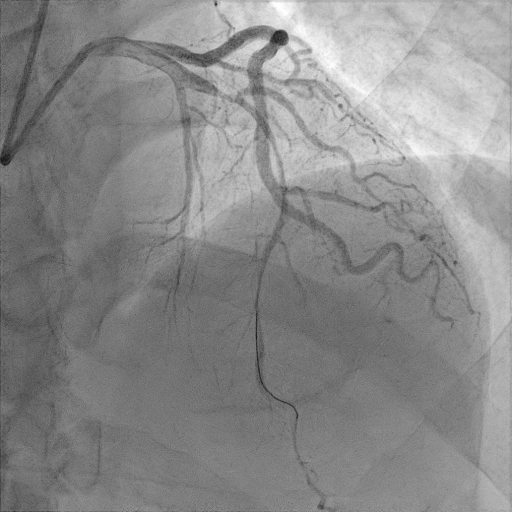

간단히 환자의 관상동맥 조영술 결과를 살펴보자

관상동맥조영술(coronary angiography) 결과 환자는 proximal LAD(left anterior descending)의 total occlusion으로 TIMI flow** 0점이었다.

관상동맥 협착으로 혈류량을 나타내는 지표인 TIMI flow로 0점은 혈관이 완전히 막혀서 혈류가 없는 상태, 3점은 정상 혈관으로 혈류가 완전한 상태를 타나 내며 0~3점 총 4단계로 표시한다.

병변의 위치에 중재술을 마친 환자는 시술 후 합병증 발생여부 및 치료를 위해 중환자실에 입원을 하였다.